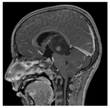

In vitro modeling of cell dissemination from hypoxic PDCL spheroids to recapitulate tumor progression in a patient. (a) Phase-contrast images and HIF-1α expression of BT68 NS in normoxic and hypoxic conditions at the indicated times. (b) Significant differential expression of seven genes involved in the hypoxia signaling pathway in cells exposed to 21% O2 versus 1% O2. (c) Diagram depicting a model of the cell dissemination from hypoxic spheroids and the immunofluorescent staining of HIFs and SOX2 (SRY-Box2) in the core and the periphery of the spheroid. (d) Quantification of the number of migrating cells. (e) Phase-contrast micrographs of PDCL migration following crystal violet staining. (f) Injected T1-weighted magnetic resonance images of patient tumors at relapse. Red arrows—distant metastasis. **** p < 0.0001; * p < 0.05. Scalebar—200 µm. DAPI: 4′,6-diamidino-2-phénylindole.

To understand the invasiveness of PDCLs in the hypoxic brain environment, we developed a spheroid in vitro model (Figure 3c) recapitulating hypoxia observed in patient brain tumors. Because the oxygen diffusion ranged from 70 µm to 200 µm in tumors and normal tissue, respectively [21], we generated spheroids (from early passages (<10) of paired MNL and NS lines) with diameters above 200 µm to create a hypoxic gradient from the periphery to the core and expanded them at 5% O2. We showed that the expression of the stem cell marker SOX2 was restricted to the periphery of the spheroid, while HIF-1α was expressed from the core to the periphery of the spheroid. We confirmed the co-expression of HIF-2α/HIF-1α and SOX2 observed in HGGs (Figure 3c). Furthermore, previous studies, comparing gene expressions in HGGs versus normal brain parenchyma, identified the extracellular matrix protein fibronectin as one of the most over-expressed gene in HGGs [22]. Then, to more carefully recreate the biology of the patient’s tumors, we immobilized the spheroids onto a fibronectin coating. The quantification of cells evading from the spheroid and the distance of migration showed that cell dissemination was slower in MNL than in their corresponding NS lines (Figure 3d). In addition, the invasiveness of each patient tumor during its progression or relapse was comparable to the migration profiles in MNL- and NS-derived spheroids (Figure 3e). As shown on MRI, the highly diffusive BT69 tumor relapse in the left thalamic initial site and in the contralateral anterior ventricle was similar to the highly invasive profile of the BT69 spheroid (Figure 3e,f). The localized BT83 tumor at relapse was comparable to the low diffusive BT83 spheroid (Figure 3e). Similar comparisons could be performed for BT68 and BT35. The SUV (standardized uptake value) on PET scans decreased in proportion to the increase of cell migration potential in the spheroid models (Figure 2c). This approach seems to confirm the importance of oxygen level variations to study in vitro cell behavior and migration.